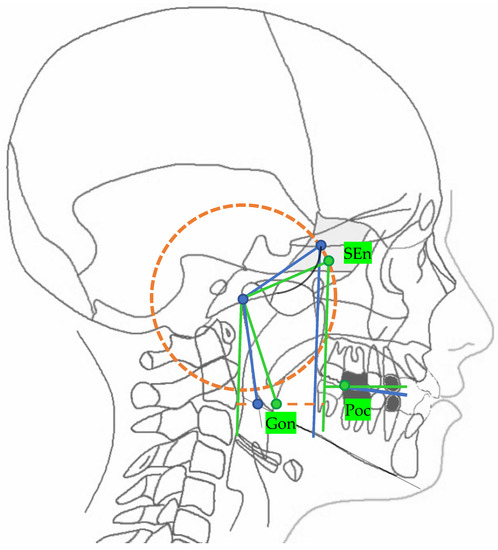

| Landmarks | |

|---|---|

| SEn | SE neutral: the point of a circumference with the center in Ar and the radius equal to the MCF, in which an angle of the skull base equal to 40.3° is obtained |

| Gon | Gonion neutral: the point located at the same level of the Go and halfway between the PMn line and its parallel passing through Ar |

| Lines | |

| PMn | PM neutral: the line parallel to the PM forming at the point SEn an ideal angle of 40.3° with the MCFn |

| MCFn | MCF neutral, Ar—Sen |

| MRn | MR neutral, Ar—Gon |

| FOPn | FOP neutral, plane perpendicular to the PMn passing through Poc |